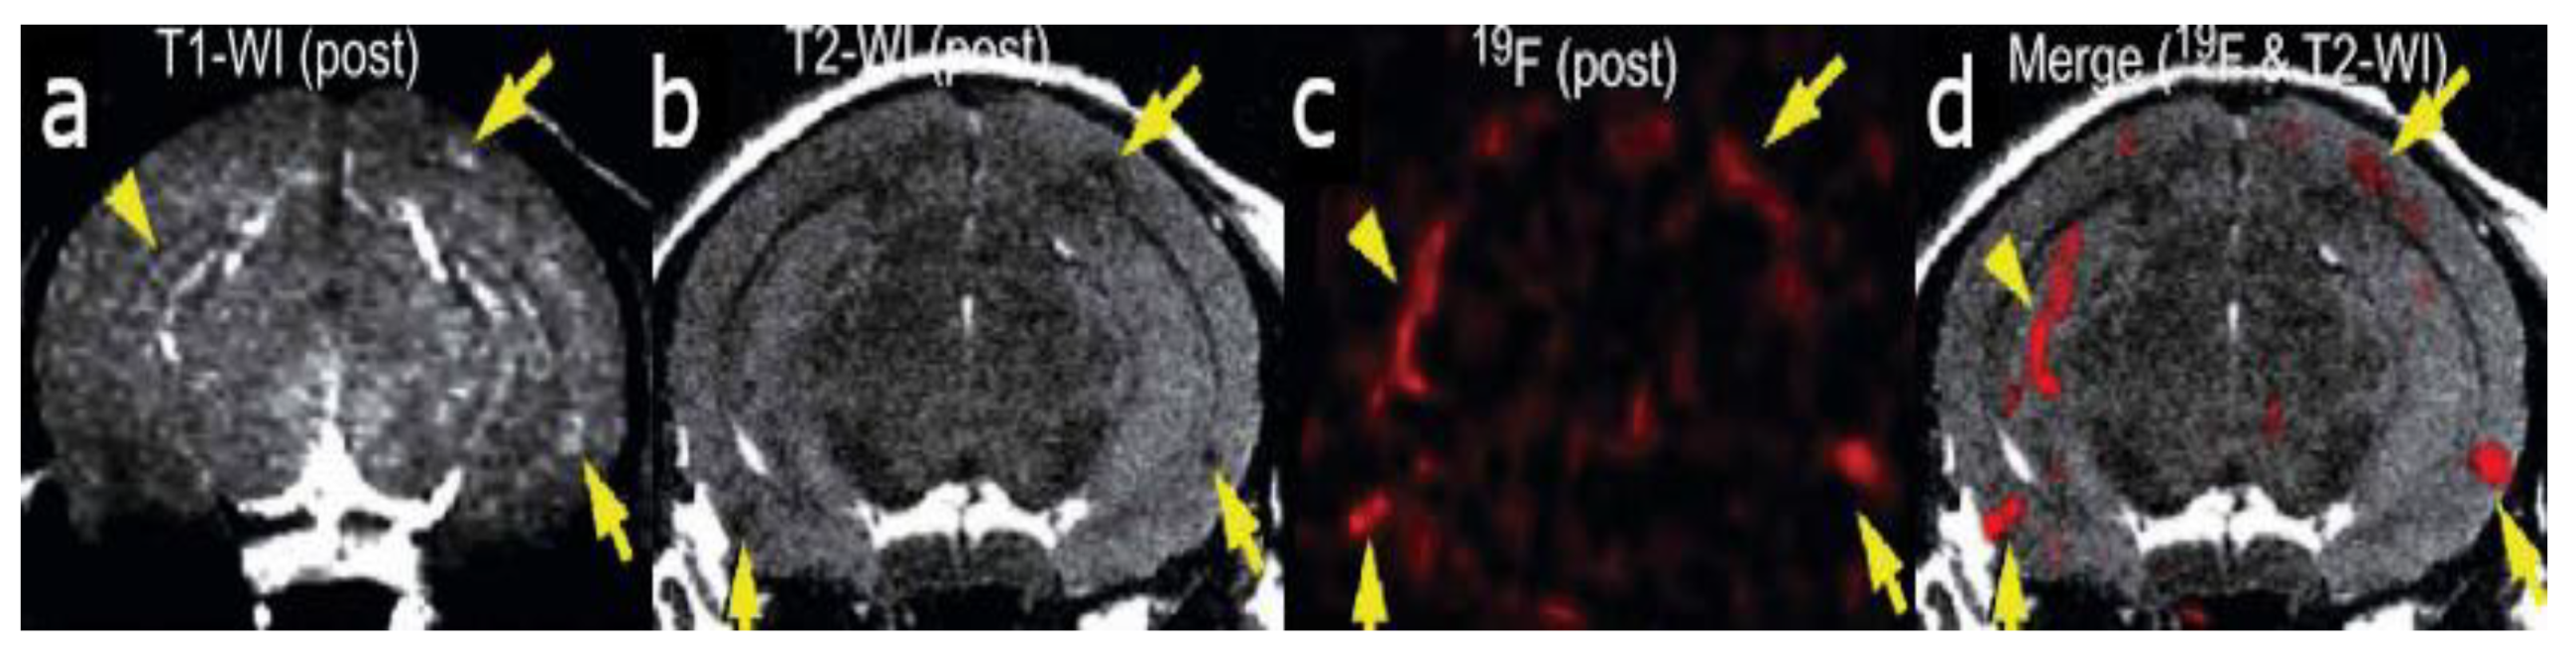

The aggregation of tau protein into neurofibrillary tangles (NFTs) represents a pathological hallmark of AD. Bundles of paired helical filaments (PHFs) comprise the NFTs and contain abnormally hyperphosphorylated tau in a β-sheet conformation [29,30,31]. It is known that tau NFT deposition correlates with cognitive decline in AD [4]. Thus, tau imaging within the brain can contribute to a minimally invasive diagnosis of AD, as well as a way to monitor disease activity and target engagement. The first study to report the detection of tau pathology using 19F-MRI employed the use of a styrl-benzoxazole derivative [32]. It has been previously reported that styrl-benzoxazole derivatives do not show binding to NFTs in AD brain sections [26]; however, compounds with a 15–18 Å of pi-electron-conjugated backbone show a high affinity to pathological tau [33]. Thus, to enhance the affinity of styrl-benzoxazole derivatives to tau pathologies, a double bond can be added to the pi-electron-conjugated backbone [32]. Recently, a buta-1,3-diene derivative, 1-(6-alkoxybenzoxazol-2-yl)-4-(4-dime-thylaminophenyl)-buta-1,3-dions (Shiga-X35), has been synthesized as a 19F MRI probe to detect NFTs. MR imaging of a live, transgenic mouse head after the injection of Shiga-X35 showed an accumulation of 19F-MR signals where NFTs accumulate in the brain, suggesting that the compound can be useful to detect tau pathology with a 7.0-T MR scanner (Figure 3). However, unwanted 19F-MR signals were detected in the wild-type mouse brain, demonstrating that the specificity and selectivity of the probe to NFTs should be improved. The sensitivity should also be improved, since a high dose of the probe was required (200 mg/kg), and the quality was poor compared to tau imaging using PET [32].

Figure 3.

In vivo tau detection in wild-type (a–c) and rTg4510 (d–f) mice using 19F MRI after the injection of Shiga-X35 [32]. The proton MRI images (a,d) were used for brain localization. (b,e) 19F MRI images acquired after Shiga-X35 injection. Fluorine images were superimposed on top of high-resolution proton images (c,f). The Shiga-X35 uptake was significantly (* p = 0.044) higher in rTg4510 mice compared to the healthy controls (g). Images and graph are reprinted with permission from the publisher [32].